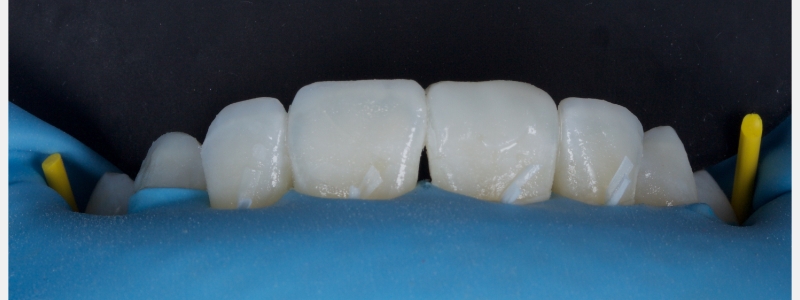

A diagnosis of altered passive eruption (APE) alongside tooth surface loss (TSL) secondary to parafunction was made for a referred female patient in her early 20s who complained of having“short, fat, baby teeth.” Due to her age, she was treated with a simple gingivectomy (after bone sounding), nightguard vital bleaching (NGVB), and additive edge bonding.

The worn incisal edges were restored with edge bonding, a new technique for restoring worn dentition. This should be regarded as a multiple Class IV restoration.